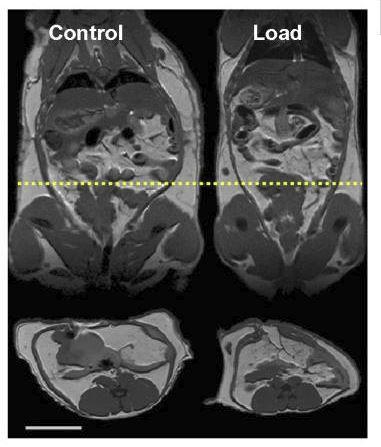

Hay un estudio muy interesante donde se les implantaron cápsulas con “mini pesas” en el abdomen a roedores obesos (muy parecido a hacer rucking)12.

Los roedores comenzaron a perder peso de forma espontánea después de esta intervención:

Al final del experimento, el peso total (peso biológico + peso de los implantes) fue similar entre los 2 grupos:

Además, el grupo con la carga extra (“Load” en la imagen de abajo) llegó a perder más grasa corporal que el grupo de control (seguían pesando más por las mini pesas, pero su peso biológico llegó a ser menor):